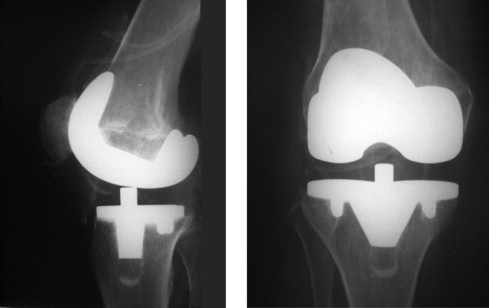

Ortopedia e Traumatologia | Cirurgia do Joelho